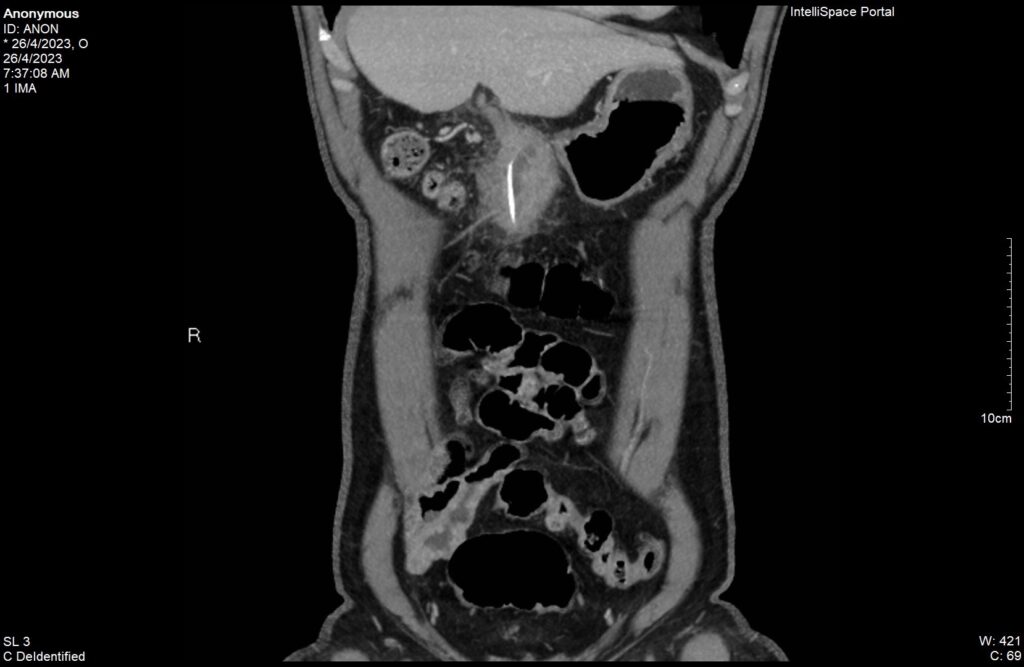

Dù đã tự uống thuốc giảm đau nhưng không thuyên giảm, cơn đau càng ngày càng tăng nên nhập viện cấp cứu. ThS. BS Phạm Hoàng Thiên- Trưởng Khoa Cấp cứu, BV Hoàn Mỹ Sài Gòn người trực tiếp tiếp nhận bệnh cho biết “Qua thăm khám ban đầu tại khoa Cấp cứu, nghi ngờ có khối áp xe ổ bụng trên người bệnh có các bệnh mạn tính nặng như tăng huyết áp, bệnh tim thiếu máu cục bộ, đái tháo đường, suy thượng thận và viêm dạ dày, chúng tôi tiến hành cho người bệnh chụp CT bụng và vùng chậu bằng thuốc cản quang. Kết quả cho thấy người bệnh bị áp xe ổ bụng vùng trước hang môn vị dạ dày do có dị vật dạng que thẳng dài 40mm, đường kính ngang 2mm nghi đâm xuyên thành dạ dày ra ngoài”

Phim CT ghi nhận dị vật trong đường tiêu hóa